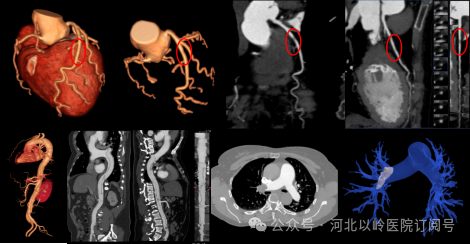

心脏冠状动脉成像

机架0.25s的超高转速,可在单次心动周期内即完成冠脉检查扫描,使得冠状动脉检查成功率接近100%,在冠状动脉血管病变的筛查、冠状动脉支架和搭桥血管评价等方面极具优势。相对于传统CT做冠脉CTA检查,超高端螺旋CT设备在患者有心律过高、心律不齐或房颤等情况下,依旧可以获得清晰的图像,这对于心血管疾病的诊断和治疗具有重要意义。

头颈部血管成像技术

对于头颈部血管大范围成像,可同时观察颈总动脉、颈内动脉、颈外动脉、椎动脉以及颅内动脉如大脑前、中、后动脉等是否有动脉瘤形成、是否有斑块形成、斑块性质分析、管腔是否有狭窄、狭窄程度分析、是否存在低灌注等情况,对于脑缺血、脑梗塞可以早期发现、准确定位。

全身大范围扫描

覆盖范围广,短时间内完成检查,多种后处理分析软件能显示细小分支,可清晰显示动脉瘤、血管畸形、血管狭窄闭塞、动脉粥样硬化斑块、主动脉夹层、肿瘤血管等。